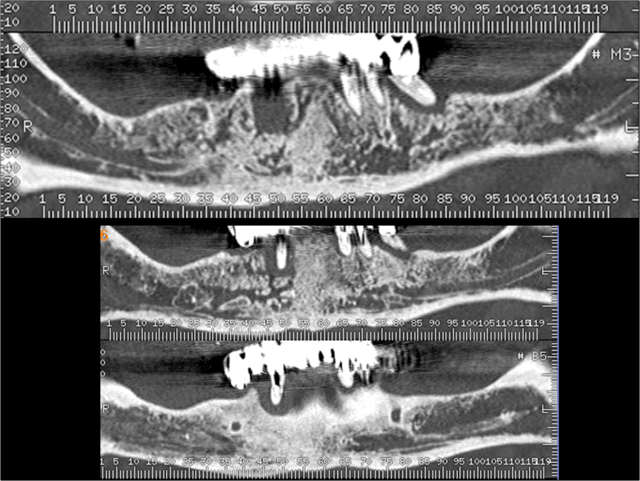

Etude en vue d'une extraction implantation pour la réalisation d'un bridge transvissé sur implants master-L.

Compte tenu de l'ampleur des lésions periapicales, l'implantation immediate est dans ce cas contre indiquée.

Complément d'information.

Je veux juste soulever la présence de ces lésions apicales qui sont TRES étendues. Il y a lésions apicales et LESIONS APICALES. Celles là n'ont rien à voir avec les lésions apicales que Lindeboom (2006) avaient dans le matériel de son étude sur l'implantation immédiate dans des sites présentant des lésion périapicales.

Même si l'implantation ne se fait pas dans les alvéoles infectées, l'implantation en est tout de même très voisine. Il y a-t-il un de vous sur ce forum qui peut m'assurer que le tissus osseux souffrant d'une activité inflammatoire ne se cantonne qu'en périphérie de la dite lésion apicale ?

En ce qui ME concerne dans un cas pareil avec des lésions apicales de cette ampleur, c'est extraction, attente de cicatrisation pdt au minimum 2 mois et installation implantaire.